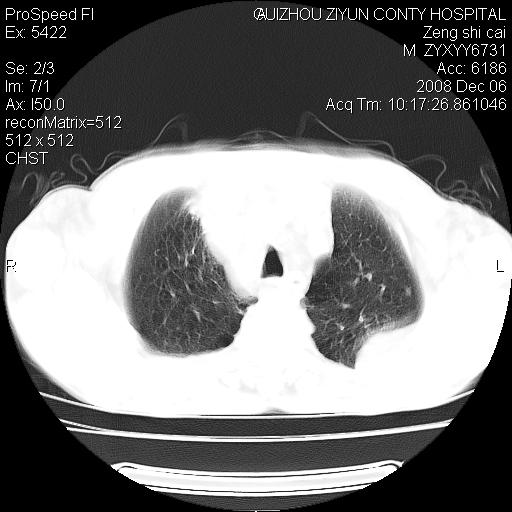

标题: CT16961:M、71岁,咳嗽半年,无血痰;胸片示右肺占位。 [打印本页]

标题: CT16961:M、71岁,咳嗽半年,无血痰;胸片示右肺占位。

右肺癌并纵隔淋巴结及胸膜转移可能性大

右肺癌并纵隔淋巴结及胸膜转移。建议气管镜

右肺纵隔型肺癌伴纵隔淋巴结及胸膜转移!

右肺纵隔型肺癌伴纵隔淋巴结转移!双侧胸水!

1)考虑右肺上叶纵隔型肺癌伴纵隔淋巴结转移。2)心包积液,双侧胸腔积液。

右肺癌并纵隔淋巴转移,腹膜后转移可能性大,两侧胸腔积液

右肺上叶纵隔型肺癌伴纵隔淋巴结转移。心包积液,双侧胸腔积液。

右上肺癌并纵隔淋巴结及胸膜转移。

建议强化!主要鉴别是淋巴瘤与肺癌淋巴结转移。

右肺纵隔型肺癌伴纵隔淋巴结及胸膜转移